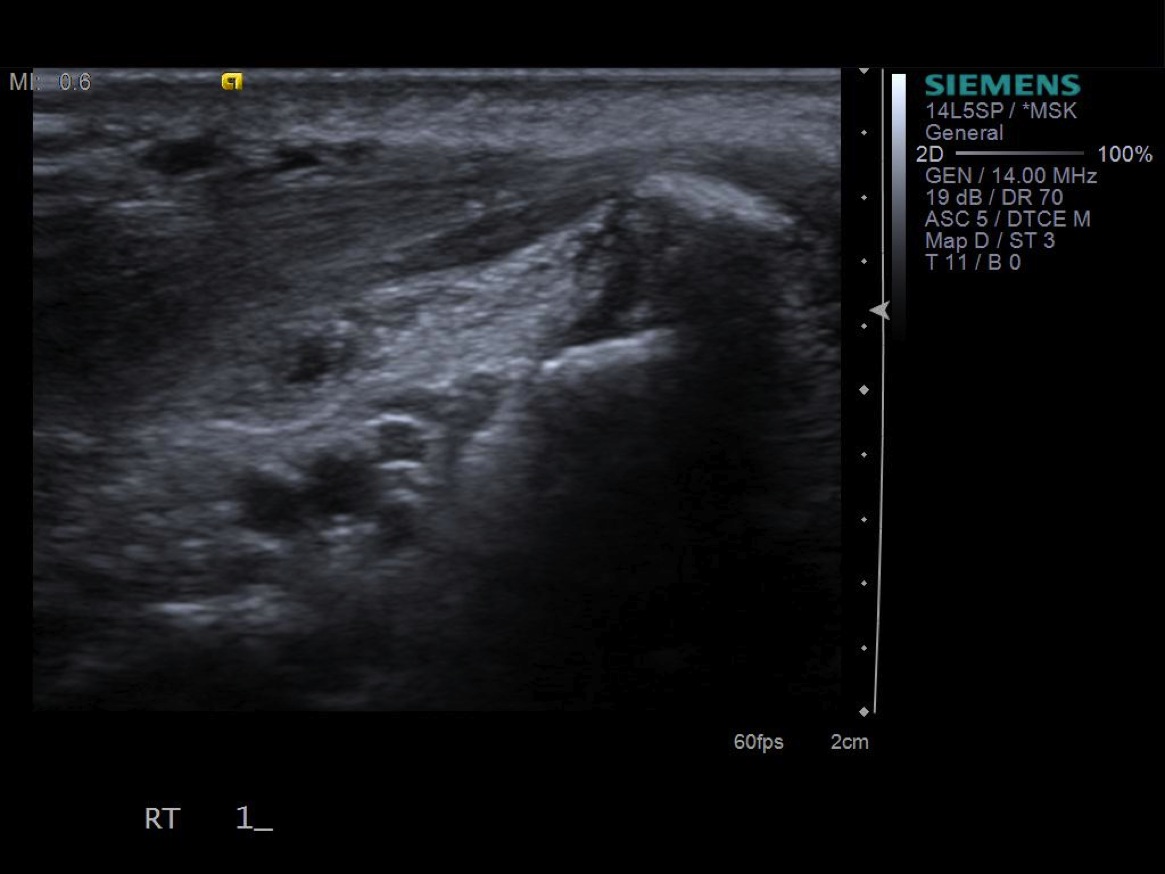

7. Under ultrasound guidance,advance needle into the 1st extensor tendon sheath. In this case the APL and EPB have separate sheaths and require their own injections. Test inject with 1% lidocaine. If no resistance, switch 1% lidocaine for injectable steroid mixture. If there is resistance, reposition needle and test inject again. Inject 1 cc of injectable steroid/anesthetic mixture.